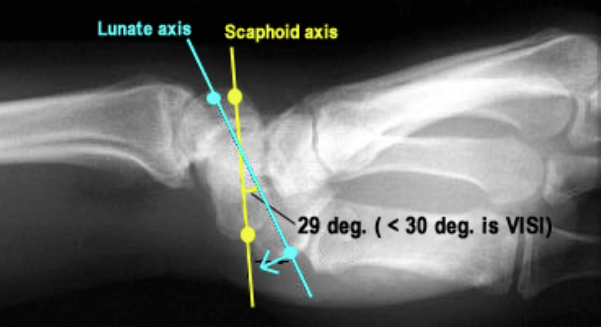

Lateral